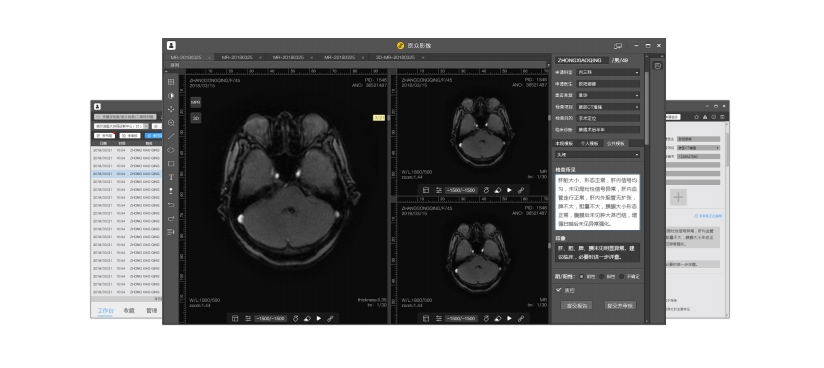

云圖診斷是一款面向醫(yī)聯(lián)體的遠(yuǎn)程影像診斷云平臺(tái)?;鶎俞t(yī)院上傳影像檔案至云平臺(tái),中心醫(yī)院或診斷中心接受請(qǐng)求,調(diào)閱影像、撰寫(xiě)診斷報(bào)告,實(shí)現(xiàn)區(qū)域內(nèi)影像診斷協(xié)同工作。

平臺(tái)主要解決基層醫(yī)院影像科人才缺乏,影像檔案分析困難的問(wèn)題。

微至云動(dòng)云影像是一個(gè)RIS/PACS系統(tǒng),提供醫(yī)學(xué)影像(DICOM)的接入、存儲(chǔ)、及調(diào)閱的公有云SaaS(軟件即服務(wù))服務(wù),已接入多家人工智能(AI)引擎?;跇O速DICOM HTML5 Viewer純HTML5瀏覽器端MPR、MIP、VR、CPR三維重建,支持PET/CT融合/SUV測(cè)量;支持跨平臺(tái)影像互操作;低投入高可用的SaaS收費(fèi)模式。